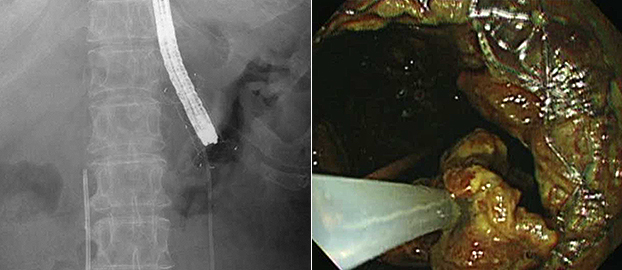

Both the proximal and distal anchor flanges are designed to hold tissue layers tight and prevent stent migration. The large lumen diameter yields effective drainage, and the short body length and the high stability enable the easy insertion of a standard upper endoscope into the cyst for direct endoscopic necrosectomy(DEN) and EUS-guided transluminal drainage (EUS-TD)1

| A Standard upper endoscope was directly advanced via the stent and Necrotic tissue was removed using a snare forceps safety with 16mm of stent diameter | ||

| The distal flange was deployed under EUS and Fluoroscopic guidance and the necrotic fluid was drained through the stent due to long enough length of stent after the stent placement | ||